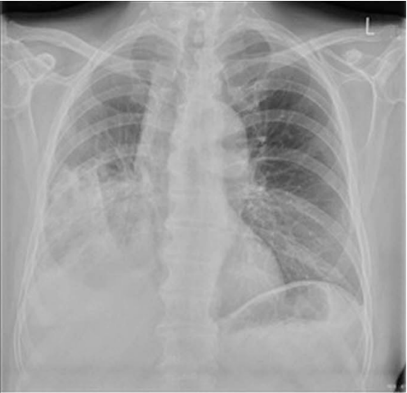

在停用免疫抑制剂并使用多种抗生素治疗后,患者症状缓解。然而,在入院7天后,他睡醒时感到呼吸困难,并出现咳嗽、胸痛和微量咯血。复查胸片见图2。检查结果显示,右上肺实变消退和新的右下肺实变,伴有右侧膈肌和右心缘清晰度的丧失。

图2 复查胸片